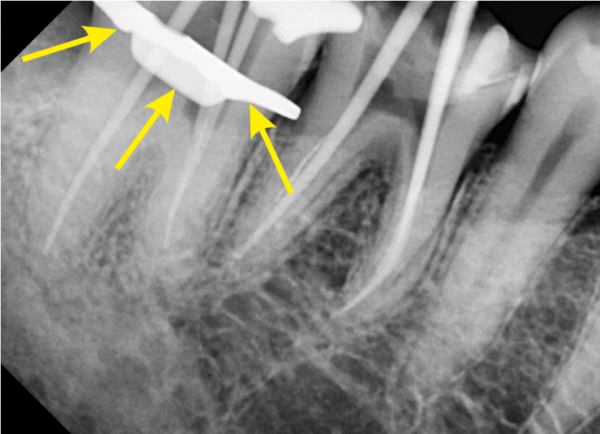

신경치료를 진행하는 상태의 엑스레이 사진입니다.

클램프로 러버댐을 고정하여 신경치료를 진행합니다.

This is an X-ray of the state of neurotherapy.

Fix the rubber dam with a clamp to proceed with neurotherapy.

신경치료를 할때는 완벽한 방습환경을 만들어 치료중에

오염이 되지 않도록 하는것이 아주 중요하기 때문입니다.

만약 이 과정에서 오염물질이 들어가게되면 신경치료를 끝냈어도

다시 문제가 생길 수 있습니다.

When you do neurotherapy, you create a perfect moisture-proof environment.

Because it's very important not to be contaminated.

If any contaminants are found in this process, even if you're done with nerve therapy,

Problems may arise again.

저희 태평역치과 더서울치과에서는 그러한 문제가 생기지 않도록

완벽하게 방습환경을 만들어 놓고 이렇게 근관 속에 빈틈없이 수복재료가

들어갈 수 있도록 신경치료를 진행합니다.

Taepyeong Station Dental Clinic, The Seoul Dental Clinic, to prevent such problems,

It's a perfect moisture-proof environment, and the restorative ingredients in the root canal

Neurotherapy is performed so that you can enter.